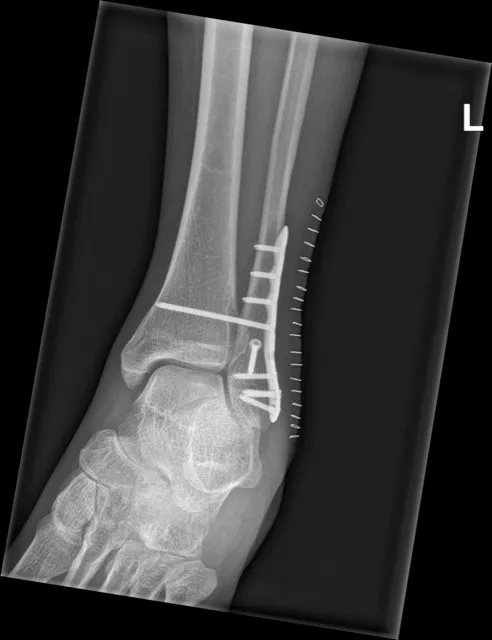

Stap 2: Operatieve behandeling: bij een verplaatste of instabiele enkelbreuk is een operatie meestal noodzakelijk. Onder verdoving brengt de orthopedisch chirurg de botstukken weer op hun plaats (open repositie). Vervolgens worden de breuken gefixeerd met metalen platen en schroeven (osteosynthese). Soms wordt bij zeer complexe breuken eerst een externe fixateur (uitwendig frame) geplaatst om de enkel tijdelijk te stabiliseren als de weke delen erg gezwollen zijn; later volgt dan de definitieve operatie. Na de operatie krijg je een gips of walker voor enkele weken ter bescherming.